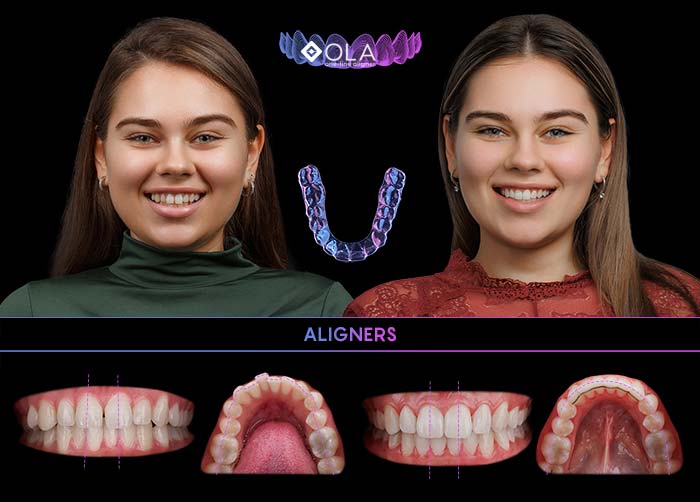

Alignerele OLA

Metoda inovativă și invizibilă de îndreptare a dinților:

Sistemul de alignere OLA, creat de Dr. Sachin Sachdev

5000+

pacienți au obținut o dantură frumos aliniată cu alignerele OLA

- 100% personalizate (se realizează în laboratorul dentar)

- Transparente, estetice și practic invizibile

- Eficiente la orice vârstă

- Detașabile (se îndepărtează ușor)

- Confortabile (material moale și neted)

Alignerele OLA KIDS

copii noștri merită tot ce-i mai bun

- îndreaptă dinții treptat, confortabil și fără durere

- se potrivesc cu stilul de viață hiperactiv al copiilor

- detașabile (se fixează ușor pe dinți)

- transparente și estetice (practic nu se observă)

- fără presiune asupra gingiilor, nu rănesc mucoasa bucală, nu distorsionează dicția